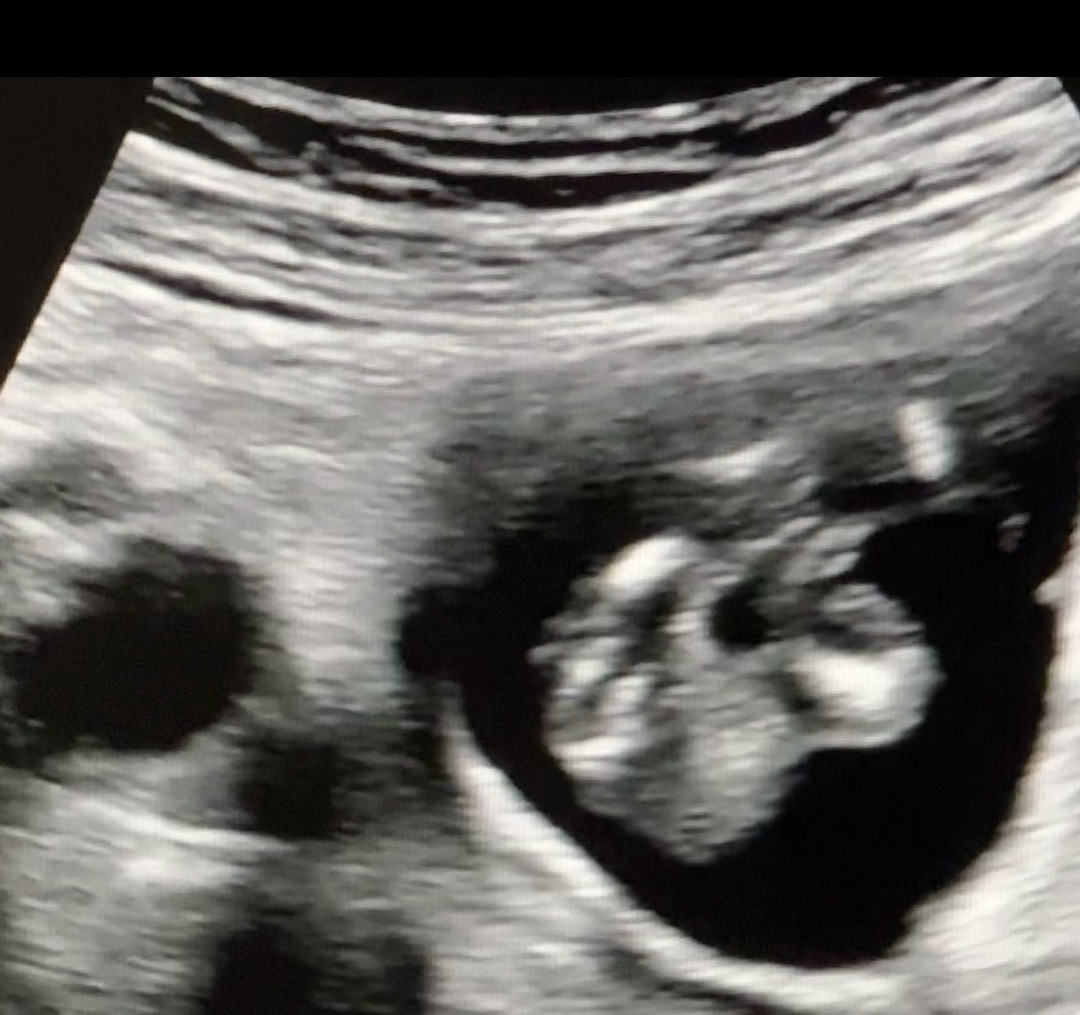

13주 5일 이정도면 🌶️확정이겠죠?ㅎㅎ

삼지창이긴한데 가운데가.. 😅